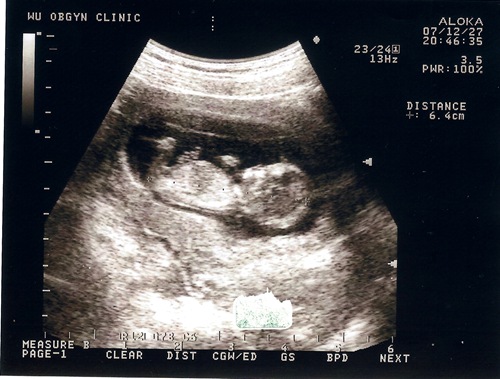

花了150塊就照了這一張超清楚的照片

從右邊的數據可以看到頭臀長己經有6.4公分了

嗯.. 不錯

有乖乖在長大

每次照完超音波我們都很high.. 這次照得超清楚~~ 真好!!